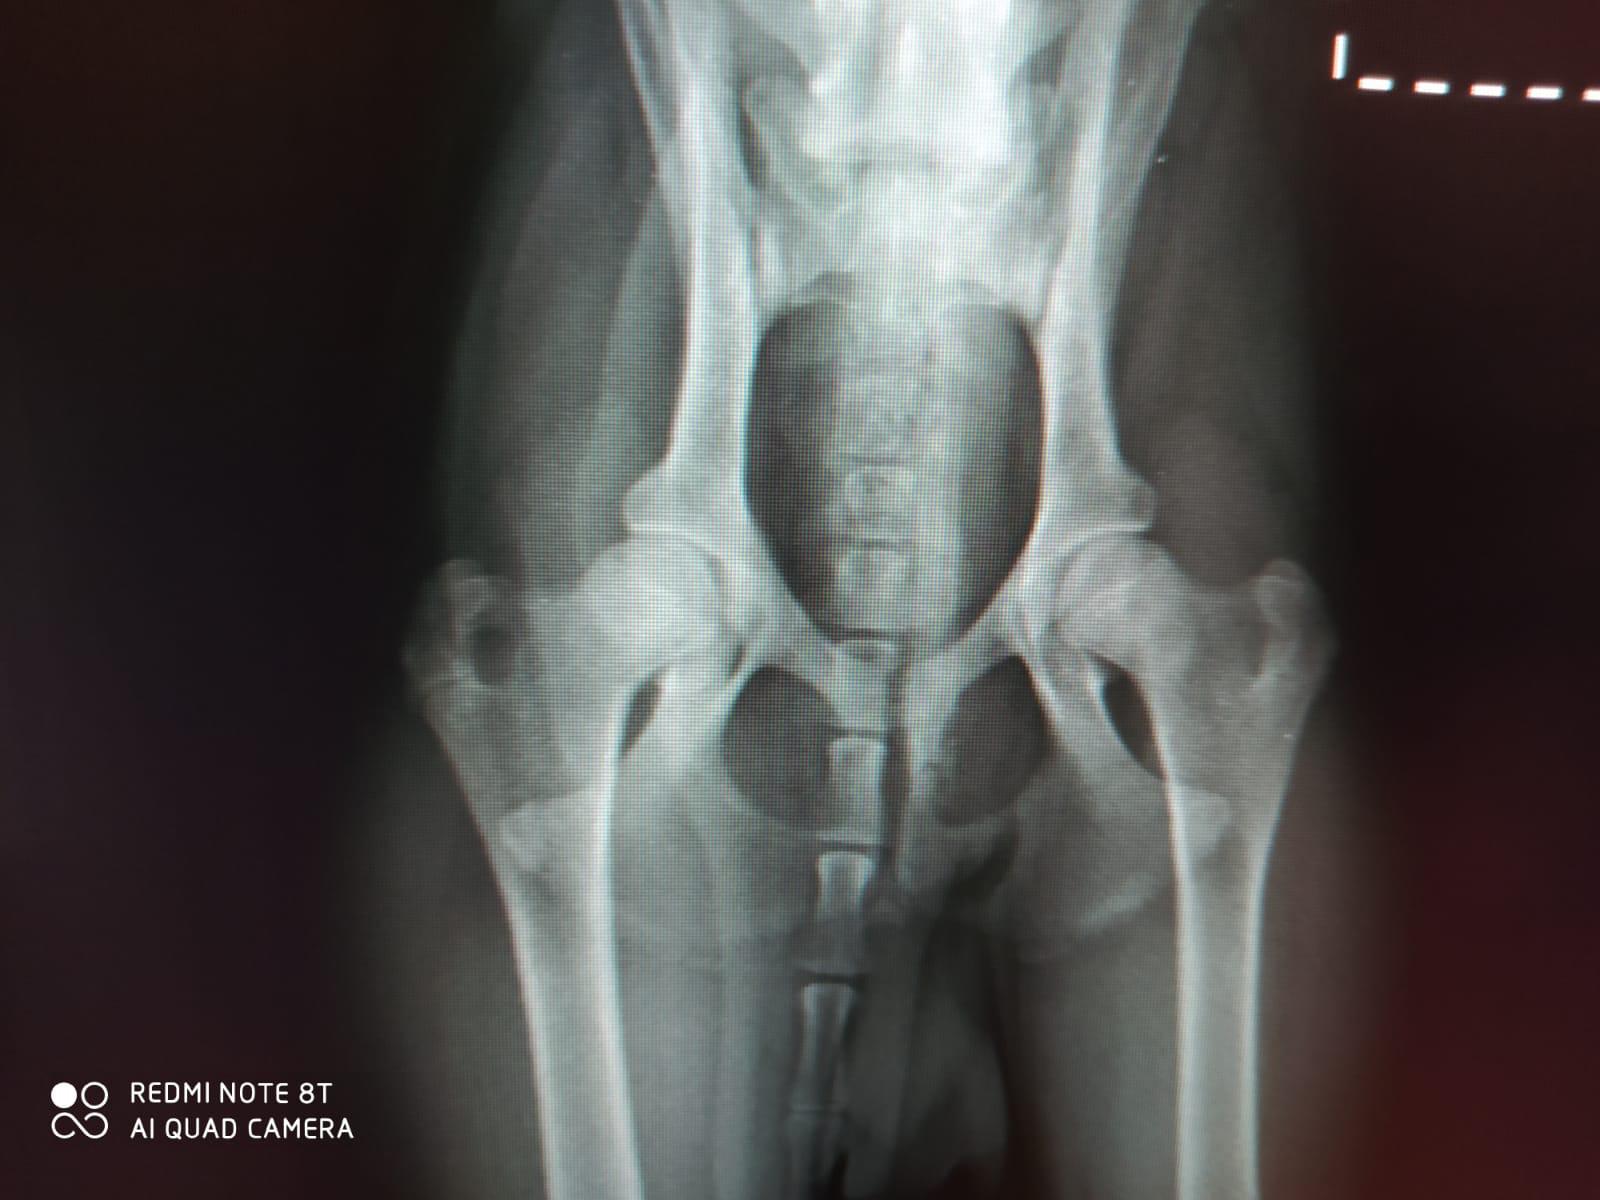

Zitat von Luitgard am 9. Februar 2024, 14:57 UhrBill wurde gezüchtet, um ein Jagdchampion zu werden und wurde leider zum Notfall. In der Wachstumsphase zeigte er Probleme beim Laufen. Tierärztliche Untersuchungen ergaben eine beidseitige "Bilaterale Abtrennung des Schienbeinkamms". Das ist eine für junge Hunde typische Verletzung, bei der sich der Teil des Schienbeins ablöst, der in der Wachstumsphase noch nicht fest mit dem restlichen Knochen verwachsen ist. Zwar ist eine Operation möglich, aber die zu erwartenden Kosten entmutigten den Besitzer so sehr, dass er sogar eine Euthanasie in Betracht zog. Schließlich bat er unseren italienischen Partnerverein, Bill zu übernehmen.

Bill wurde gezüchtet, um ein Jagdchampion zu werden und wurde leider zum Notfall. In der Wachstumsphase zeigte er Probleme beim Laufen. Tierärztliche Untersuchungen ergaben eine beidseitige "Bilaterale Abtrennung des Schienbeinkamms". Das ist eine für junge Hunde typische Verletzung, bei der sich der Teil des Schienbeins ablöst, der in der Wachstumsphase noch nicht fest mit dem restlichen Knochen verwachsen ist. Zwar ist eine Operation möglich, aber die zu erwartenden Kosten entmutigten den Besitzer so sehr, dass er sogar eine Euthanasie in Betracht zog. Schließlich bat er unseren italienischen Partnerverein, Bill zu übernehmen.